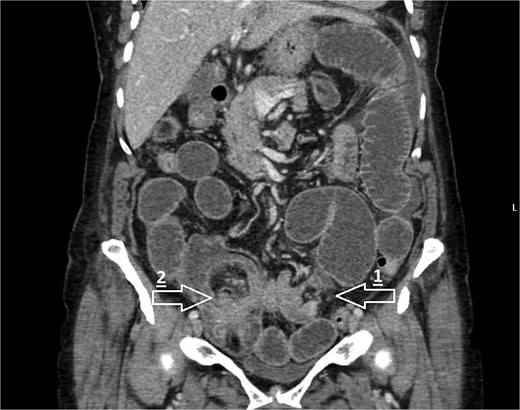

Computed tomography (CT) of the abdomen and pelvis showed high-grade small bowel obstruction secondary to ileo-caecal intussusception with a large segment of the small bowel and its mesentery invaginating into the caecum (Fig. 1).

CT coronal image demonstrating small bowel obstruction secondary to ileo-colic intussusception with large segment of small bowel invaginating into caecum. Arrows mark the following: 1—transition point of bowel obstruction, 2—ileo-caecal intussusception ‘lead point’.